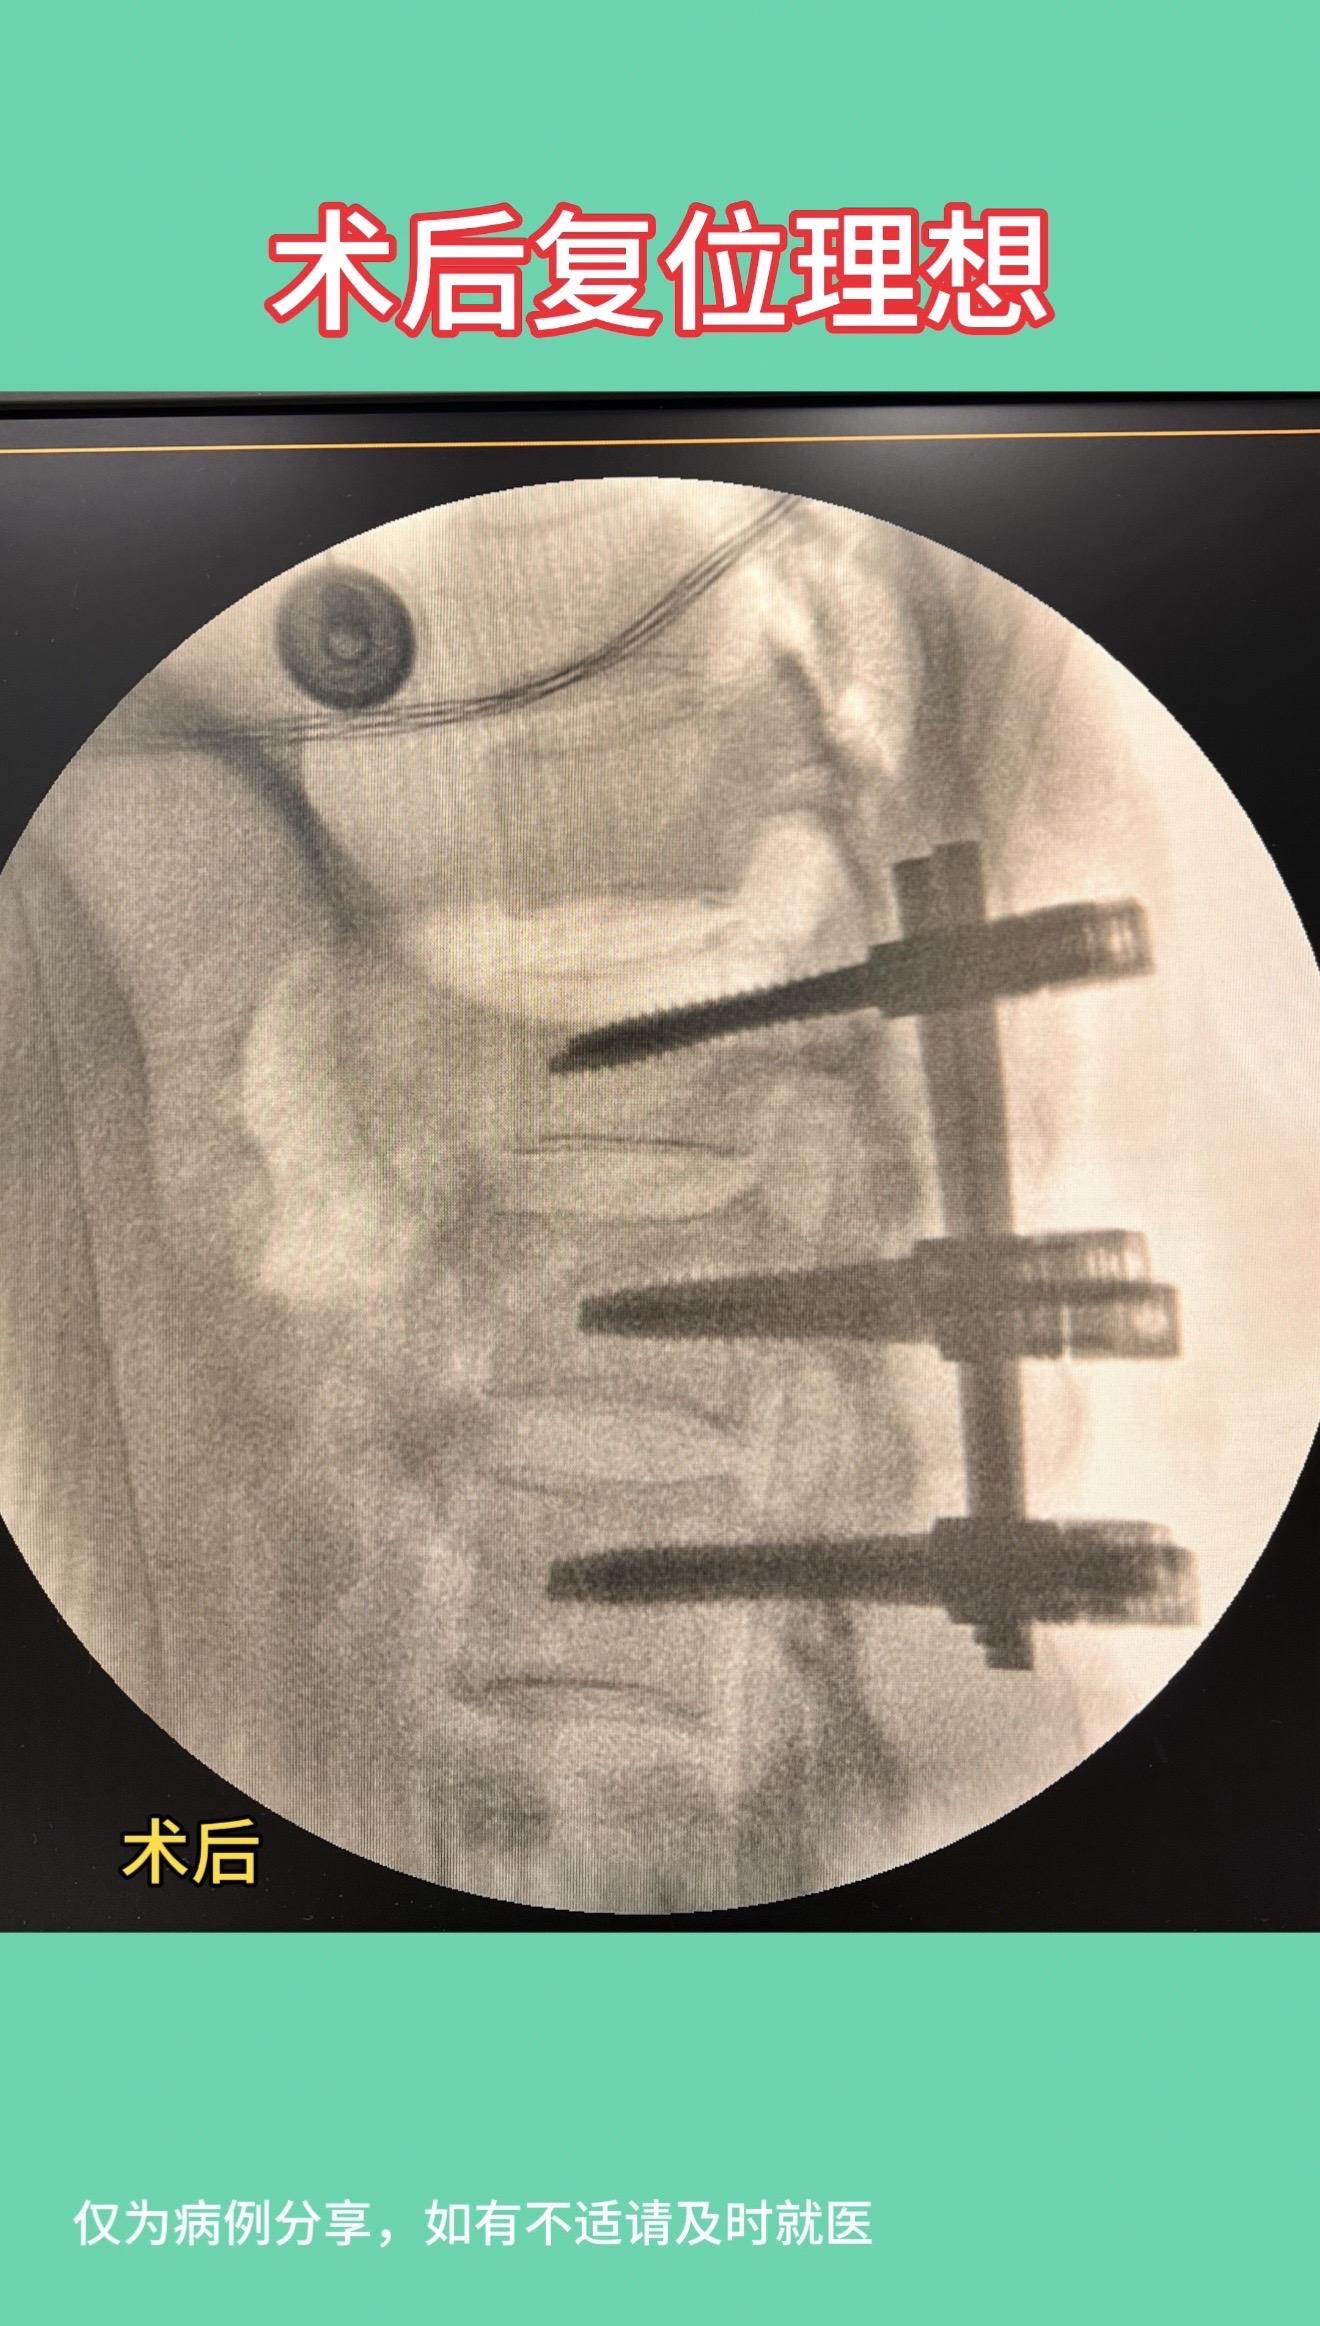

50多岁女性,在家干农活时从凳子上摔下,腰1椎体骨折,手术后复位理想...

50多岁女性,在家干农活时从凳子上摔下,腰1椎体骨折,手术后复位理想,愿患者早日康复